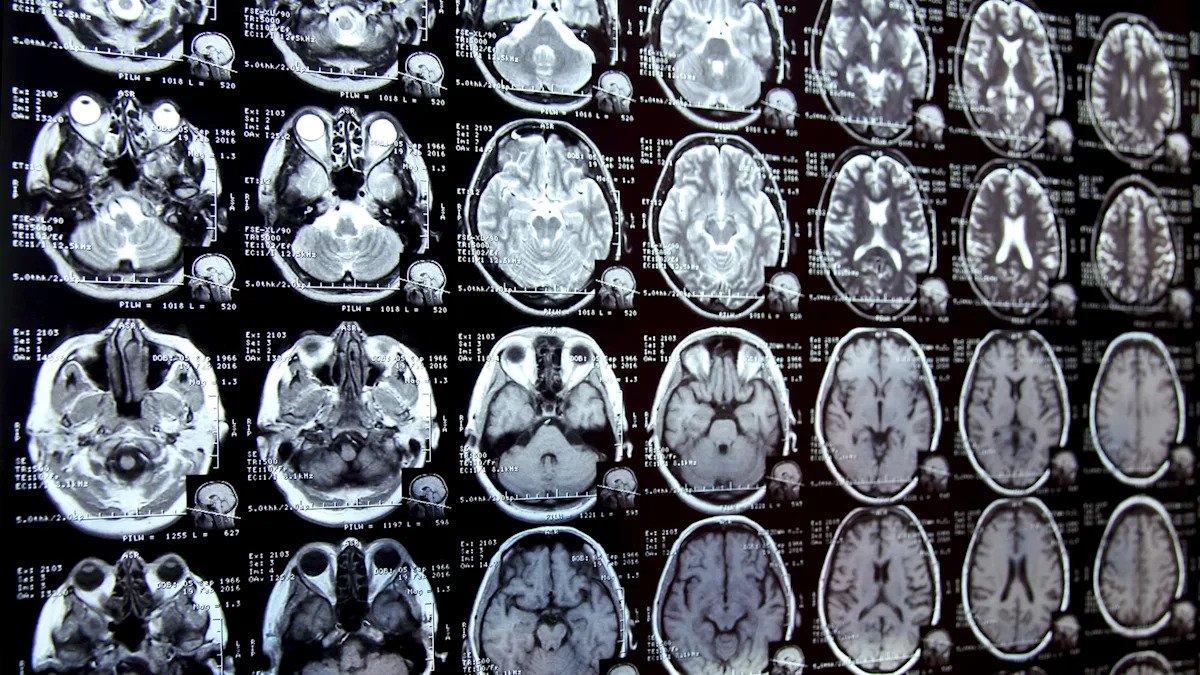

Área Estudio innovador Dirigidos por investigadores de la Universidad de Nuevo México, los científicos descubrieron que las muestras de cerebro de 2024 contienen casi un 50% más de microblastos que las de hace apenas ocho años. El cerebro normal contenía unos siete gramos de plástico, lo mismo que una cuchara desechable.

Más preocupados, los investigadores observaron niveles más altos de microblastos en los cerebros de personas con demencia, aunque, como señaló el Times, los científicos observaron en el laboratorio “que podría deberse a que ese cerebro tiene una barrera hematoencefálica más porosa y menos capaz de eliminar toxinas”. Ya se han encontrado partículas de plástico similares en el ser humano. moteadotorrente sanguíneo e incluso las primeras deposiciones del bebé.

Una vez que ingresan al cuerpo humano, algunas partículas microplásticas son tan pequeñas que pueden atravesar barreras críticas y acomodaciones en órganos como el cerebro. Aunque los científicos aún no han determinado cuánto plástico es demasiado, los primeros hallazgos de la investigación sugieren nada menos que peligroso.

El profundo sondeo del Times, que ha Muchos más detalles interesantes.Señaló que el equipo del Dr. Campden continúa su investigación y “ahora está estudiando el tejido de una sección transversal de un cerebro para descubrir si algunas regiones tienen concentraciones de microplásticos más altas y podrían estar relacionadas con problemas como el Parkinson o la pérdida de memoria”.